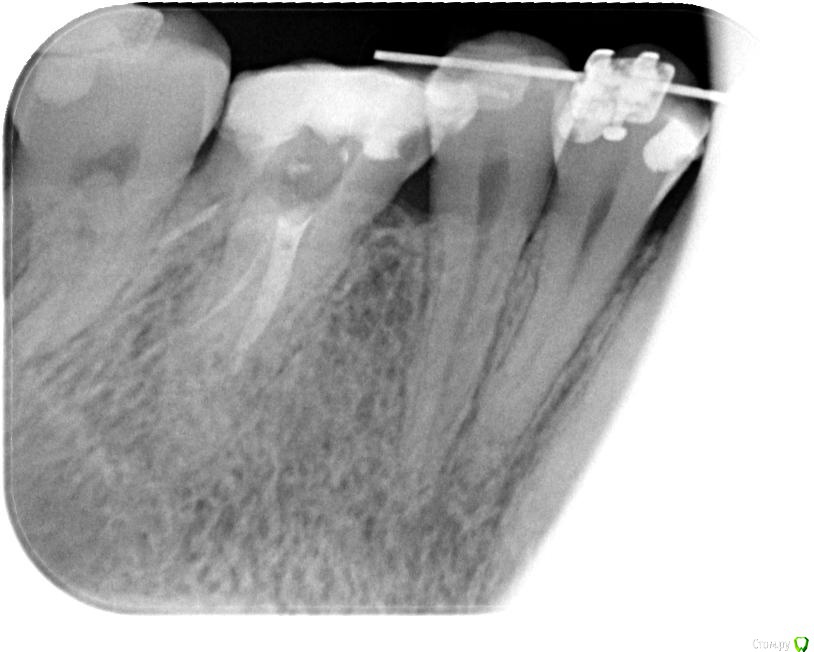

Axel_R Опубликовано 6 сентября, 2018 Автор Поделиться Опубликовано 6 сентября, 2018 Вот снимки на сегодня, зуб 26. Что скажете? Настаивать на высверливании старого материала из каналов или можно его спокойно оставить без негативных последствий? На зубе потом будет коронка. 1 1 Ссылка на комментарий

Axel_R Опубликовано 12 сентября, 2018 Автор Поделиться Опубликовано 12 сентября, 2018 Апдейт: Прошли 3 канала из 4, включая широкий небный. В оставшемся тонком канале говорят старый материал очень плотный и не поддается. На КТ и на снимках воспаления в районе верхушек тонких накалов не наблюдают и в других местах его тоже не видят. Форсировать не хотят, опасаются таки сделать перфорацию в тонком изогнутом канале. Поэтому доктор принял решение его оставить как есть и пломбировать пройденные. Ну Ок, им виднее. Но дело в том что зуб все еще болит когда кусаю что-то твердое! И никто не может назвать причину боли. Всегда думал сначала определяют в чем причина и устраняют эту причину, а уже потом пломбируют (ну как с кариесом). Я конечно мало в этом понимаю, но мне кажется если сейчас «замуровать» все вместе с источником боли, то ведь потом до этого источника уже будет не добраться (если он внутри канала или корня). А вдруг болеть будет еще неограниченно долго? Ведь не для этого я это лечение начинал…Я понимаю, что на повторное эндо нет гарантии и согласился с этим в документе, но как-то боязно... Вопрос: Правильное ли это решение? Соглашаться ли мне на пломбировку всех каналов когда зуб все еще болит? Ну или не соглашаться на завершение повторного эндо пока не устранят когда кусаю твердое? Какие будет мнения?Сама по себе пломбировка может устранить боль? Пока хожу с временной пломбой.На фото зуб в конце лечения с инструментами. Ссылка на комментарий